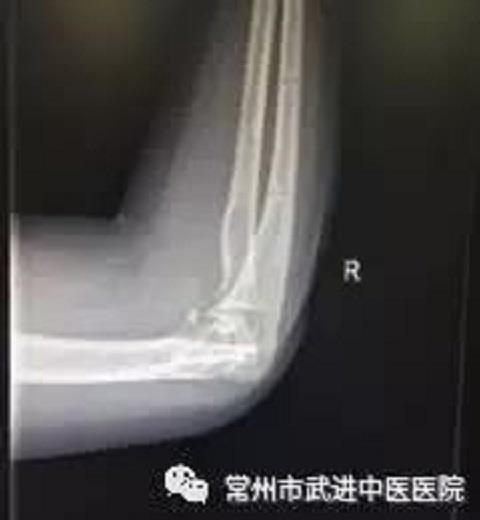

外固定拆除后DR片(下) 王女士住院后,康复医生做了详细的功能评定。

功能评定望诊:右上肢周围皮肤无红肿,肘关节处稍肿胀,右肘后可见一纵形手术疤痕,长约10cm,愈合良好。